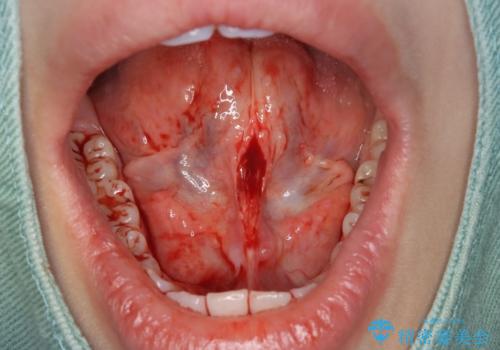

滑舌が気になる、舌小帯形成術

- 舌が動かしにくい、滑舌が気になるとのことで来院されました。

舌存在する小帯を小手術で形成することで滑舌の改善を計ります。

舌小帯形成術は、舌の下にある小帯(舌小帯)を調整する手術です。通常、舌小帯が短い場合に行われます。この手術は、滑舌の改善や発音の向上に使用されます。

手術は局所麻酔下で行われ、舌小帯を切開し、縫合します。